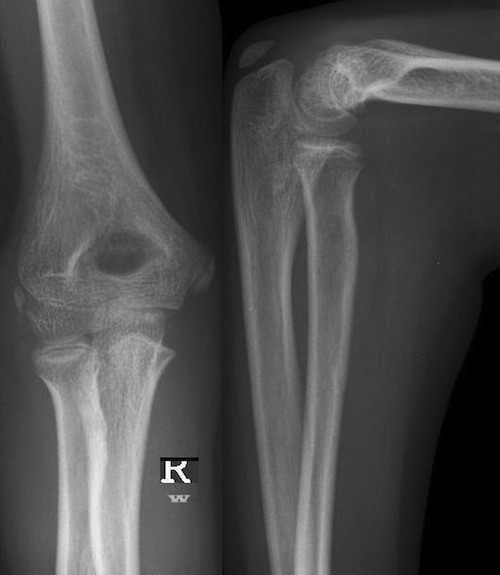

Beispiele

2/3 der Unterarmfrakturen gehen mit Frakturen von Radius und Ulna einher (komplette Unterarmfrakturen). Bei den übrigen, solitären Unterarmfrakturen kommt häufig zu Luxation/ Subluxation des nicht-frakturierten Knochens. Sonderformen:

Monteggia-Fraktur: proximale Ulnaschaftfraktur mit Dislokation des Radiusköpfchens Einteilung nach Brado.

Galeazzi-Fraktur (2): (Schräg-)Fraktur des distalen Radius mit Luxation/Subluxation im distalen Radioulnargelenk. (häufig subtil -> Hinweis: Aufweitung des Gelenkspalts, Überlagerung von distalem Radius und Ulna, im Seitbild dorsale Überlappung der Ulna)

Essex-Lopresti-Fraktur: Trümmerfraktur des Radiushalses/-köpfchens mit Einstauchung und Konsekutiver (Sub-)Luxation im distalen Radioulnargelenk.